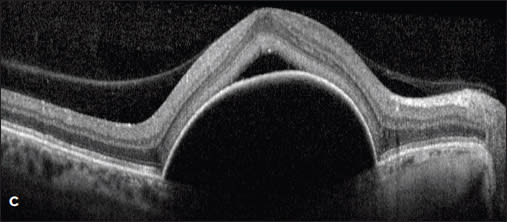

Case 3. A 78-year-old woman presented with new neovascular AMD with a PED in the right eye (Figures 3A and B). Her vision dropped from 20/25 to 20/50. After multiple treatments with ranibizumab, the PED persisted, and her vision declined to 20/80. ICG angiography was performed, and a hot spot was identified at 1 o’clock (Figure 3C). This spot was treated with PDT, with collapse of the PED and BCVA improvement to 20/32 (Figure 3D).

Figure 4. A patient with a new CNV seen on FA was treated with ranibizumab (A). The large serous PED failed to resolve (B). A focal lesion was noted at 1 o’clock by ICG (C) and was treated with PDT. The PED flattened with improved BCVA (D).